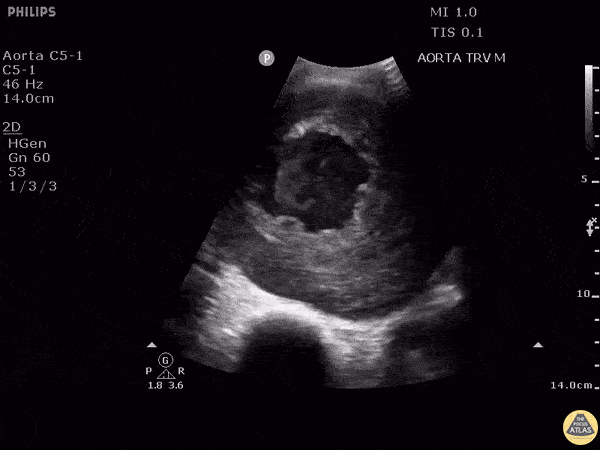

Here is another example of an abdominal aortic aneurysm that measured approximately 10.6 cm. The patient originally presented to the clinic complaining of a cough and was eventually admitted for surgical operation. Image courtesy of Robert Jones DO, FACEP @RJonesSonoEM Director, Emergency Ultrasound; MetroHealth Medical Center; Professor, Case Western Reserve Medical School, Cleveland, OH View his original post here